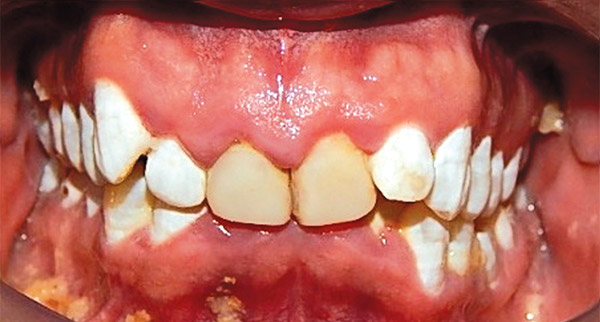

Respecto a los estudios finales intraorales, en las fotografías podemos observar la coincidencia de líneas medias dentales (Figura 19), la clase I molar y canina bilateral (Figura 20 y 21).

Figura 19.

Finalizado el tratamiento se realizaron carillas provisionales en el maxilar superior de los diente 15, 14, 13, 12, 11, 21, 22, 23, 24, 25 para su posterior rehabilitación (Figura 22) el overjet y overbite adecuado.

El tiempo total del tratamiento fue de un 1 y 8 meses, se lograron los objetivos planteados: se eliminar las manchas, se mejoró el color de los dientes. Se hizo la expansión dentoalveolar superior, Se preparó la superficie dental para el bondeo de brackets, se corrigió el apiñamiento maxilar y mandibular, se obtuvo la clase I canina y molar bilateral. Las líneas medias dentales coinciden, el overbite y overjet mejoró (Figura 25).

Respecto a la corrección de la sonrisa del paciente (Figura 26), con la restauración de protésica, cabe señalar que los dientes con fluorosis grado 1 tienen un color muy blanco, motivo por el cual la resina no pudo igualar el color, pero con las carillas ya se asemejó la tonalidad de los dientes. Finalmente la estabilidad del postratamiento a cargo de un retenedor circunferencial con cinturón vestibular superior e inferior (Figura 27).